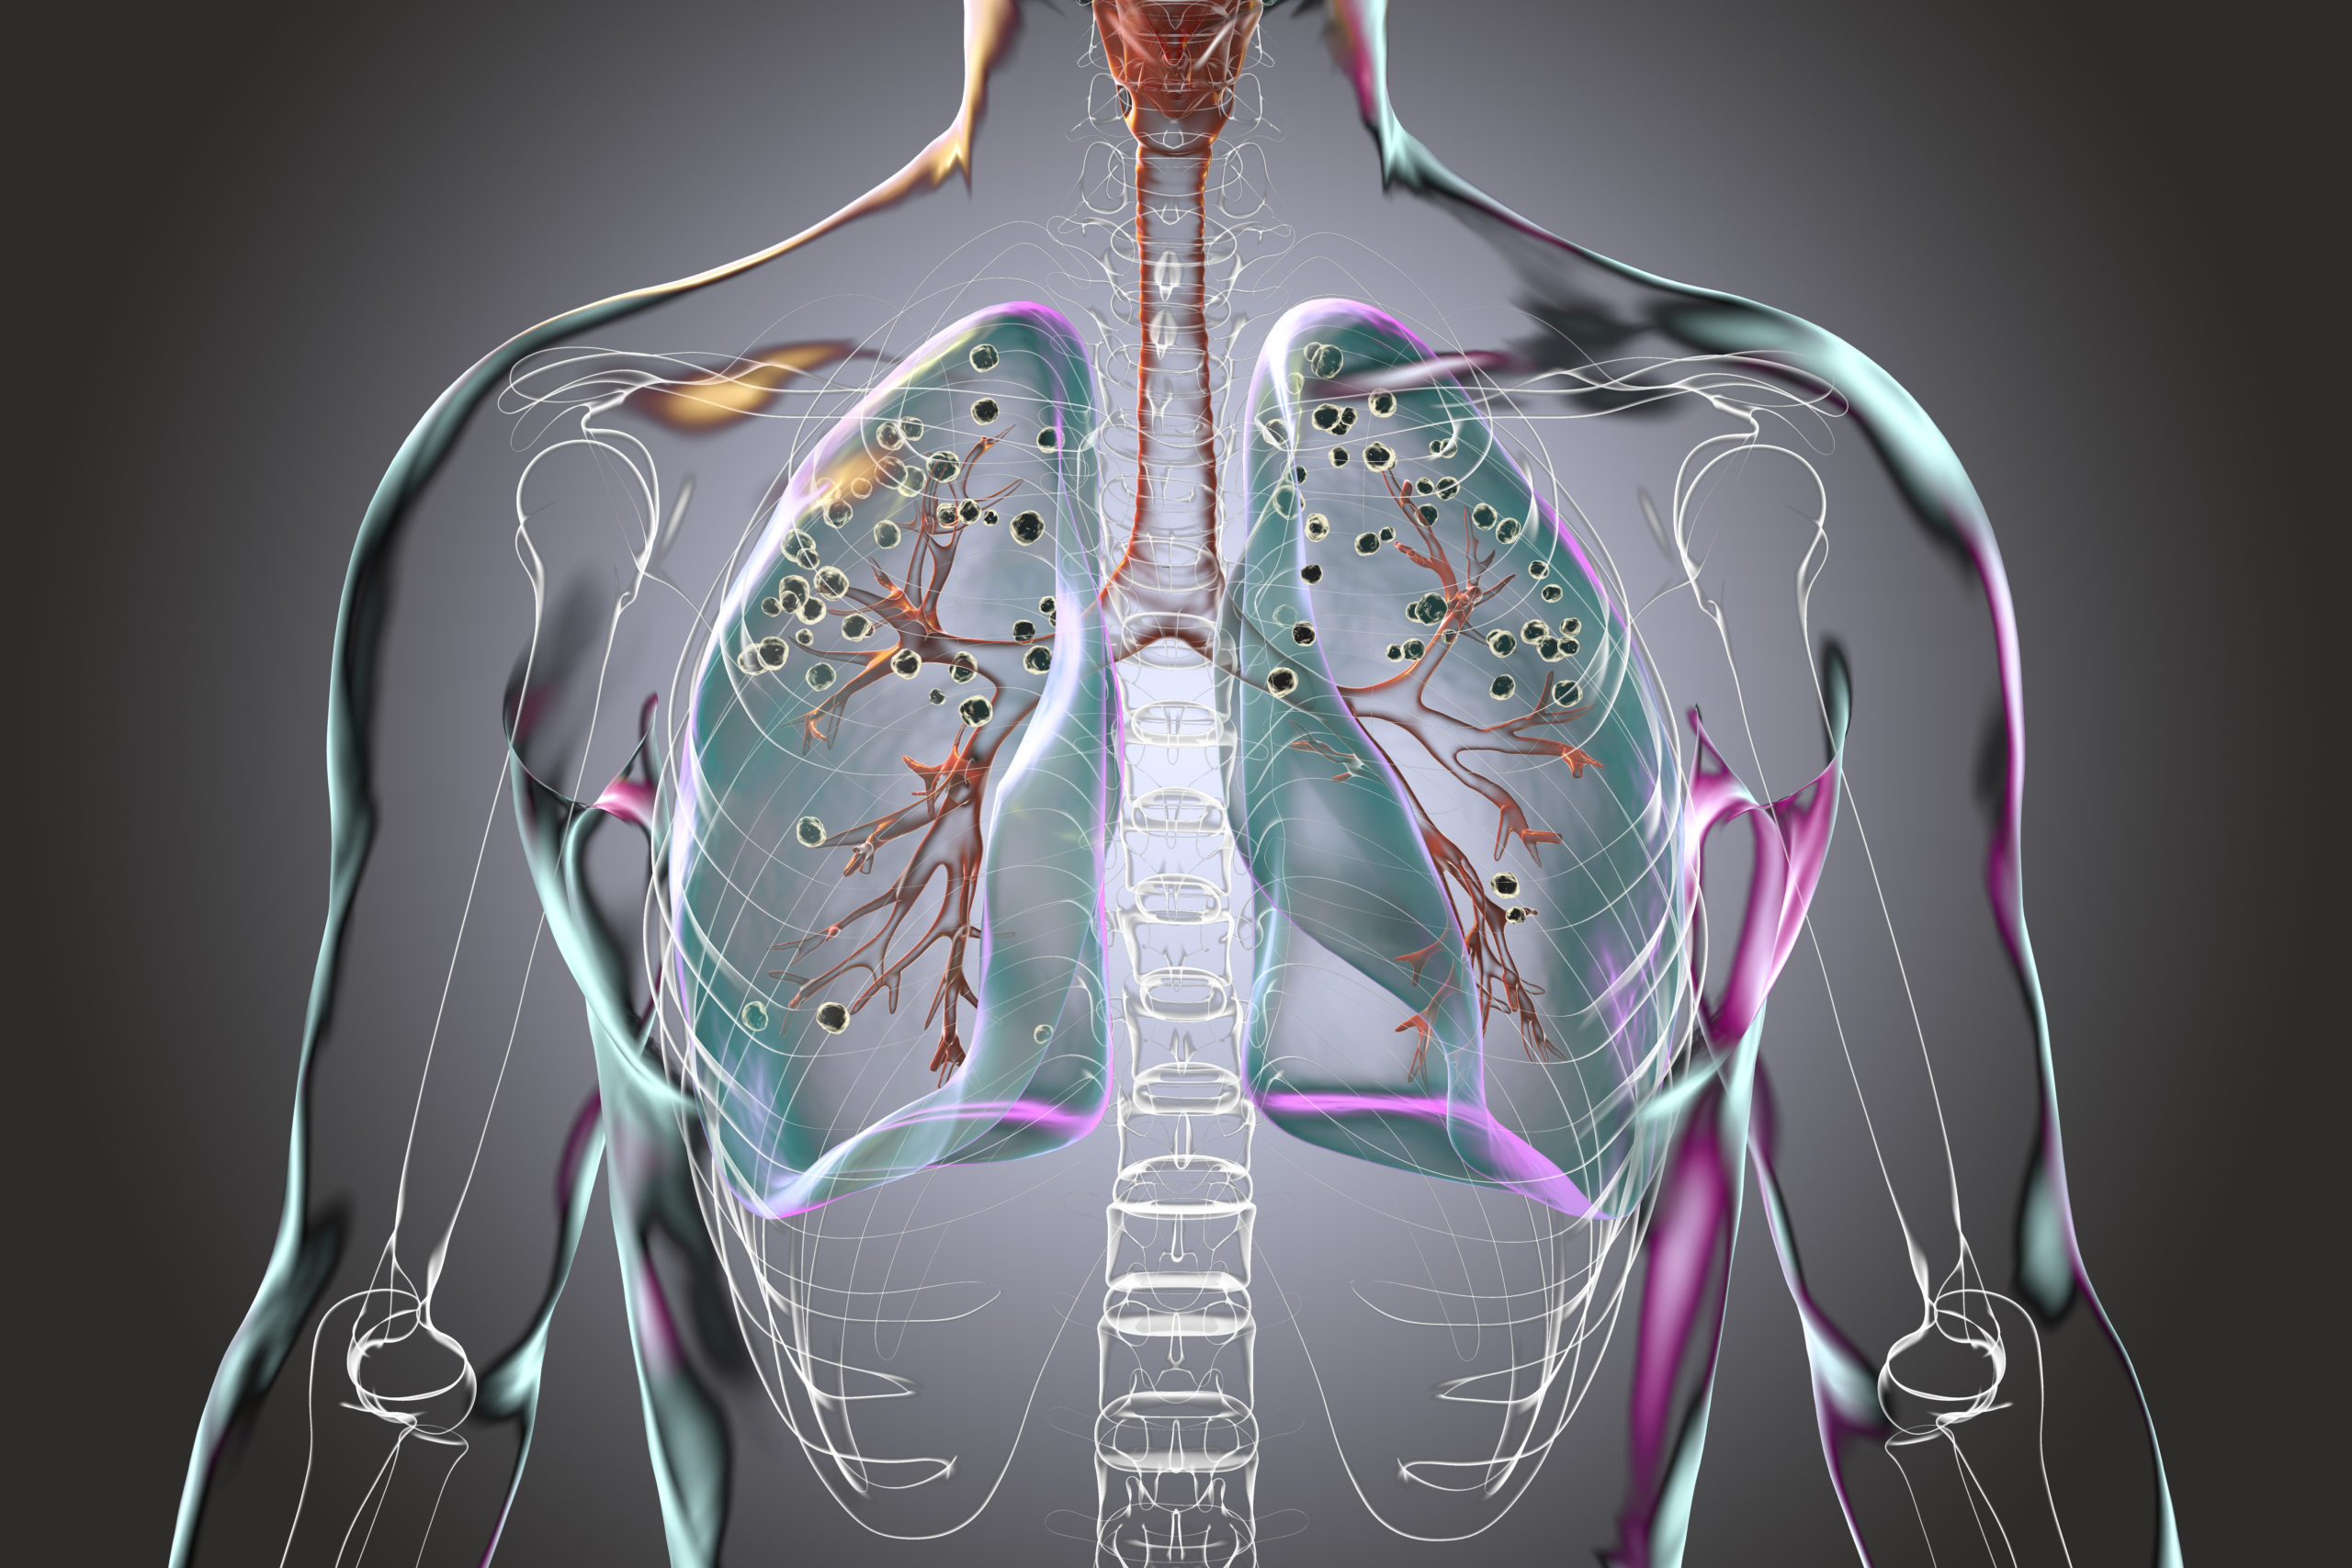

An estimated 2.3 million workers across the U.S. are exposed to an invisible and often unnoticed hazard: respirable crystalline silica dust, a substance that can lead to serious health problems including silicosis and lung cancer. To address this widespread risk, we must educate ourselves with the appropriate knowledge and tools to protect our health.

- Understanding the nature of respirable crystalline silica and its associated health hazards